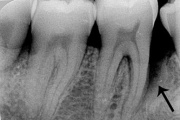

Agressiivse parodontiidi kahjustused rasedal naispatsiendil